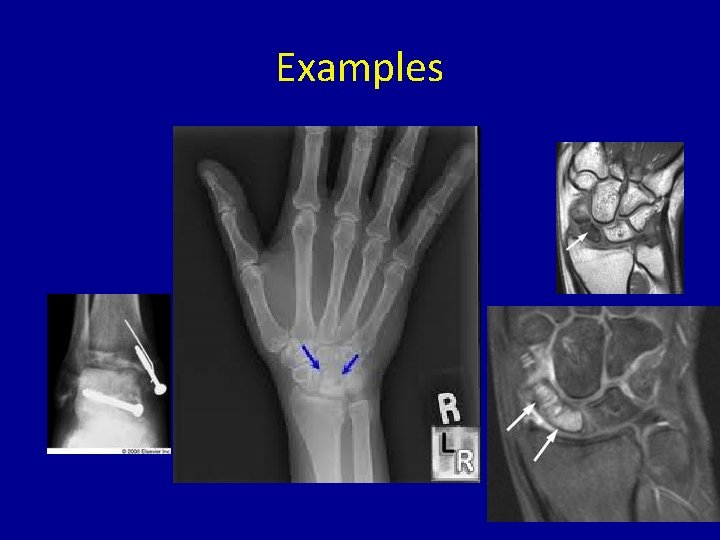

Bones Affected • • • Femoral head – most common by far Shoulder – humeral head Odontoid (Neck) Scaphoid (Wrist) Lunate (Wrist) Talus (Ankle)

Examples